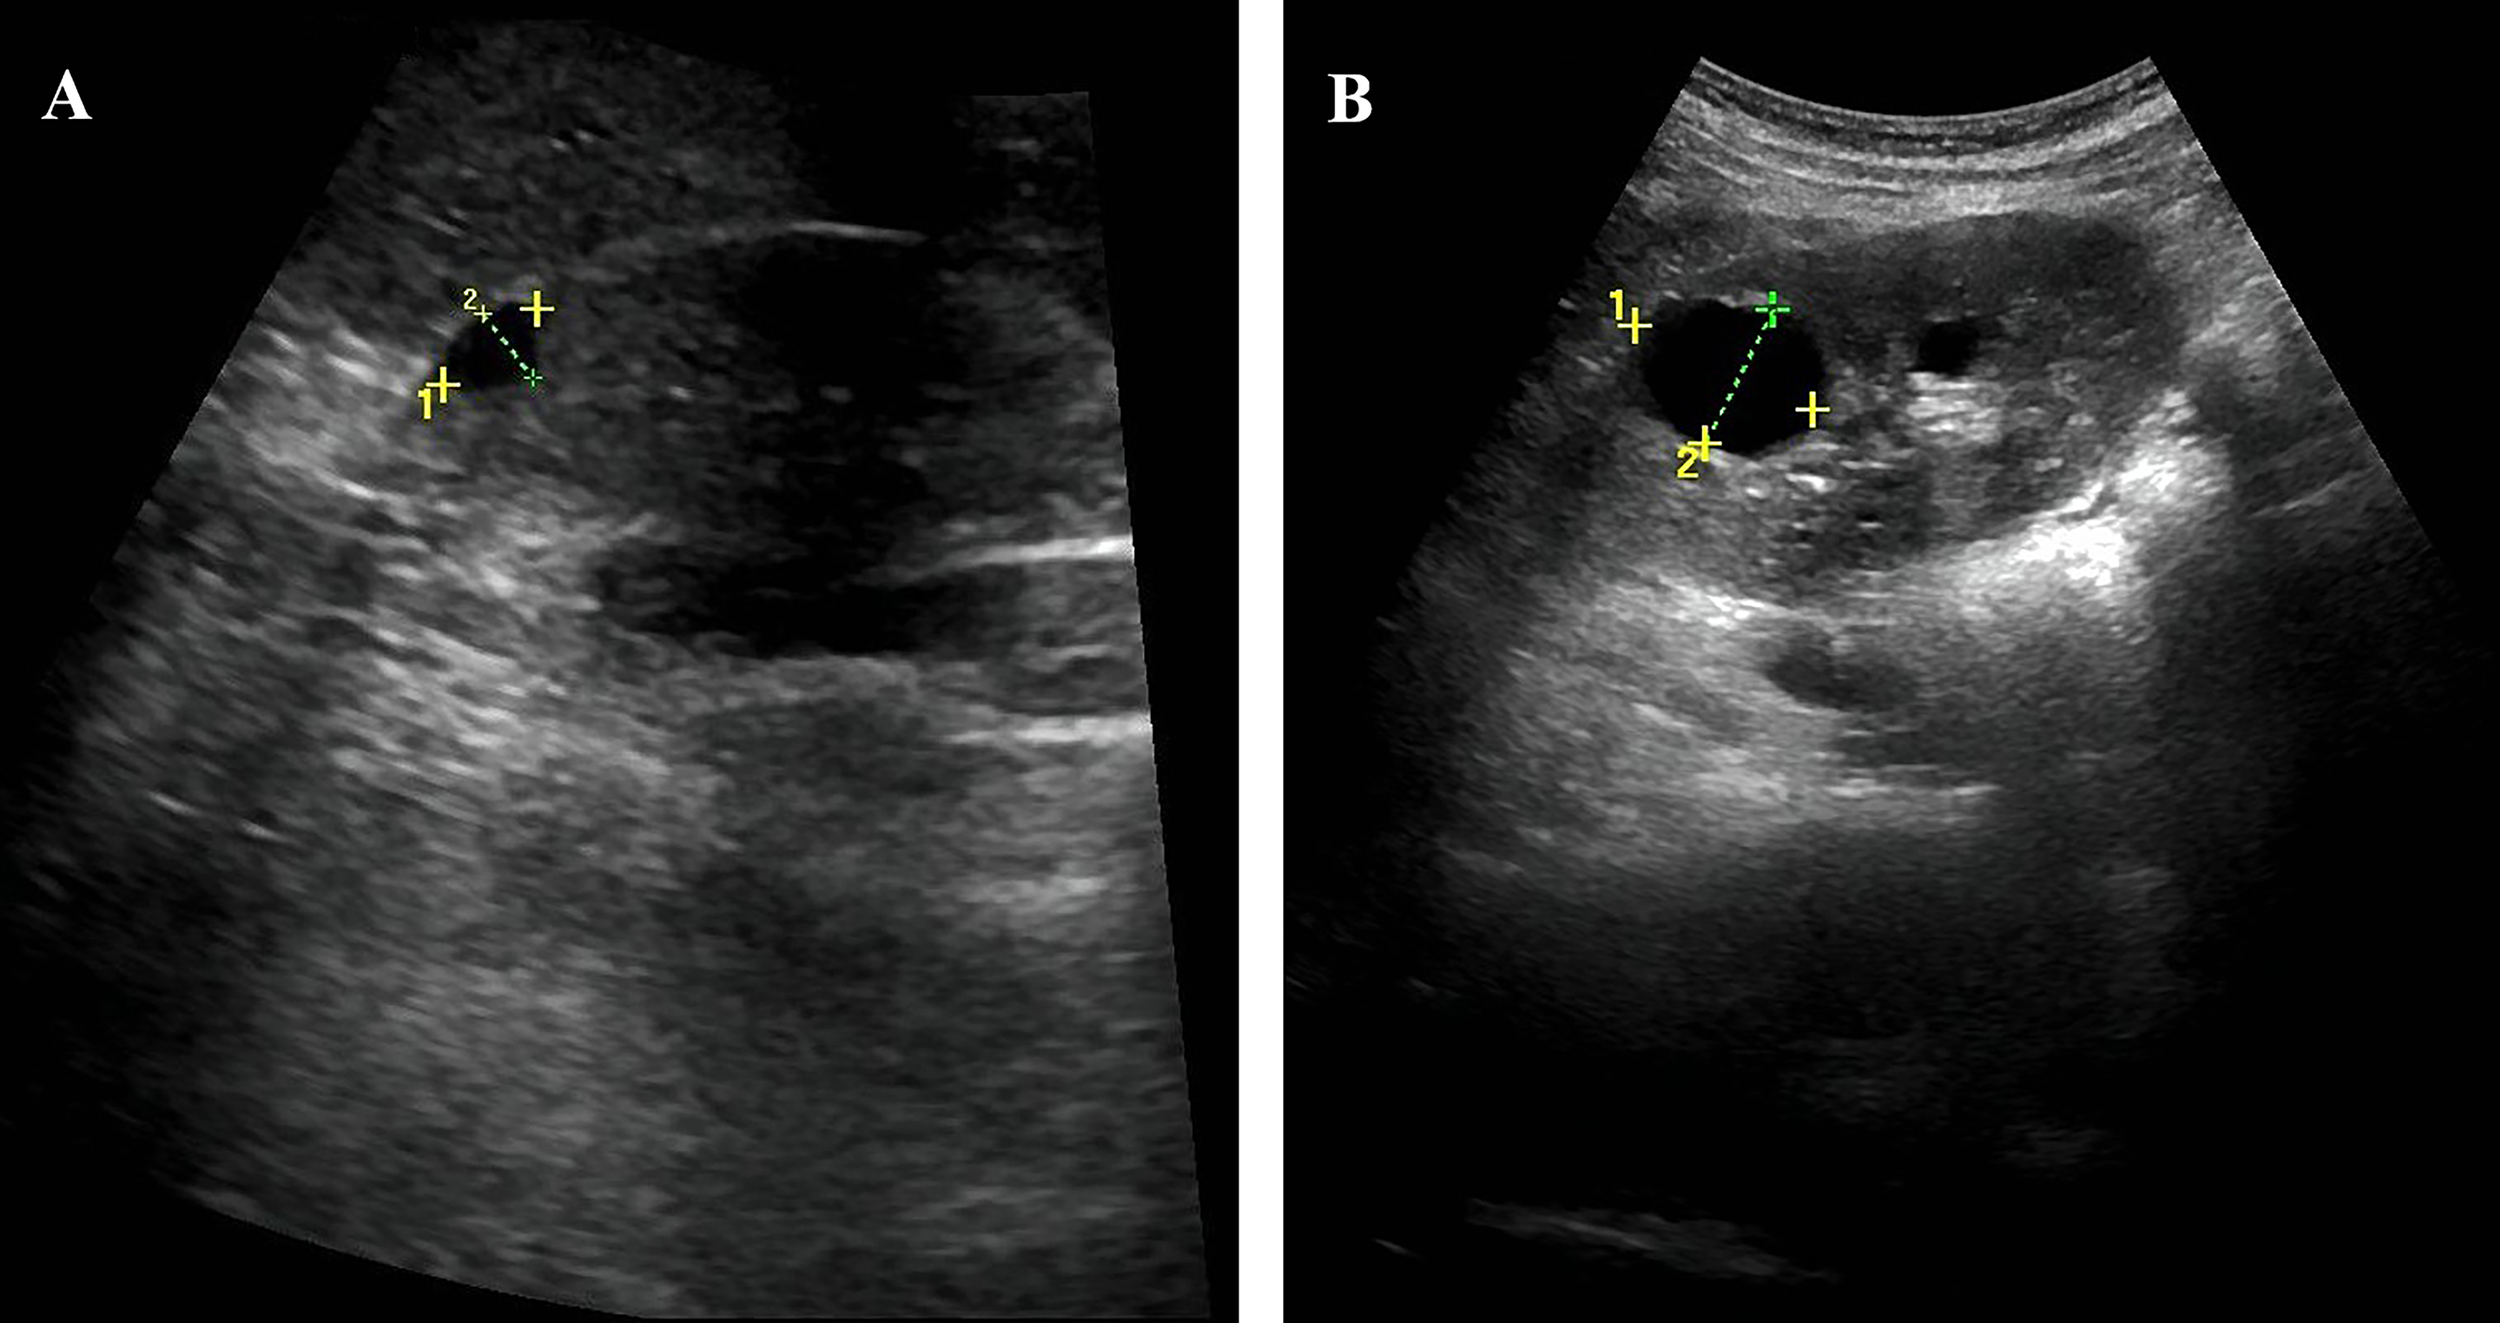

A 26-year-old Chinese woman was admitted to our hospital, with symptoms of thirst, easy hunger, and polyuria for half a year. She had no nausea, vomiting, diarrhea, abdominal pain, or blurred vision. The patient was 156 cm in height, 37.6 kg in weight, and 15.5 kg/m2 in body mass index (BMI). Physical examination revealed no abnormalities except rapid pulse rate and malnutrition. Laboratory investigations revealed a random blood glucose (RBG) level of 28.9 mmol/L and glycated hemoglobin (HbA1c) value of 17.40%. The erythrocyte sedimentation rate (ESR) level was 10 mm/h and c-reactive protein was less than 3.11 mg/L, both within the normal range. Urine ketone bodies were positive and urine sugar was strongly positive. Therefore, the patient was diagnosed with diabetic ketosis and treated with insulin at a dose of 0.48 U/kg*d as a tentative pharmacotherapy. The patient’s hyperglycemia gradually improved and urine ketones were negative. After that, we performed the relevant examination for the patient (Tables 1 and 2). The results showed that her fasting glucose (FBG) level was 9.08 mmol/L and serum C-peptide and insulin levels were 0.31 nmol/L and 2.03 uIU/mL, and 2-hour postprandial blood glucose level was 9.75 mmol/L and 2-hour postprandial serum C-peptide and 2-hour postprandial insulin levels were 0.26 nmol/L and 1.40 uIU/mL. The patient’s insulin resistance index HOMA-IR was estimated as 0.82. Serum creatinine and esti mated glomerularfiltrationrate (eGFR) were 57.00 umol/L and 129.23, respectively. Serum potassium level was low and serum magnesium level was at the lower limit of normal. As shown in Figure 1, ultra-sonographic examination of the abdomen revealed multiple cysts in both kidneys, the echogenicity of the liver parenchyma was enlarged, and no obvious abnormality was detected in other organs. To determine the pathogenesis of her diabetes, further tests were performed (Table 1). Anti-GAD, anti-IAA and anti-ICA antibodies, unique to type 1 diabetes, were all negative. The patient’s insulin secretion was insufficient, so insulin subcutaneous pump was used and the dose was maintained at 0.38 U/kg*d.

Figure 1

Abdominal ultrasound showed the patient’s kidneys. (A) The patient has multiple cysts in the right kidney, the largest cyst (9*6mm). (B) The patient has multiple cysts in the left kidney, the largest cyst (25*19mm).